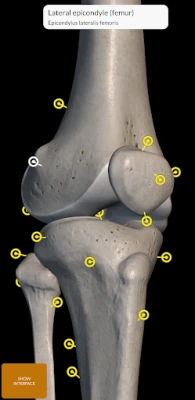

"Skeleton | 3D Atlas of Anatomy" is a next generation anatomy atlas in 3D which gives you availability of interactive highly detailed anatomical models!

Each bone of the human skeleton has been reconstructed in 3D, you can rotate and zoom in on each model and observe it in detail from any angle.

By selecting models or pins you will be shown the terms related to any specific anatomical part, you can select from 12 languages and show the terms in two languages simultaneously.

HIGHLY DETAILED ANATOMICAL 3D MODELS

• Skeletal System

• Accurate 3D modeling

• Surfaces of the skeleton with high resolution textures up to 4K

• Rotate and Zoom every model in the 3D space

• Division by regions for a clear and immediate visual of each structure

• Interactive Pin allow visualization of the term relative to every anatomical detail

• Hide / Show interface, ideal for use on smartphones